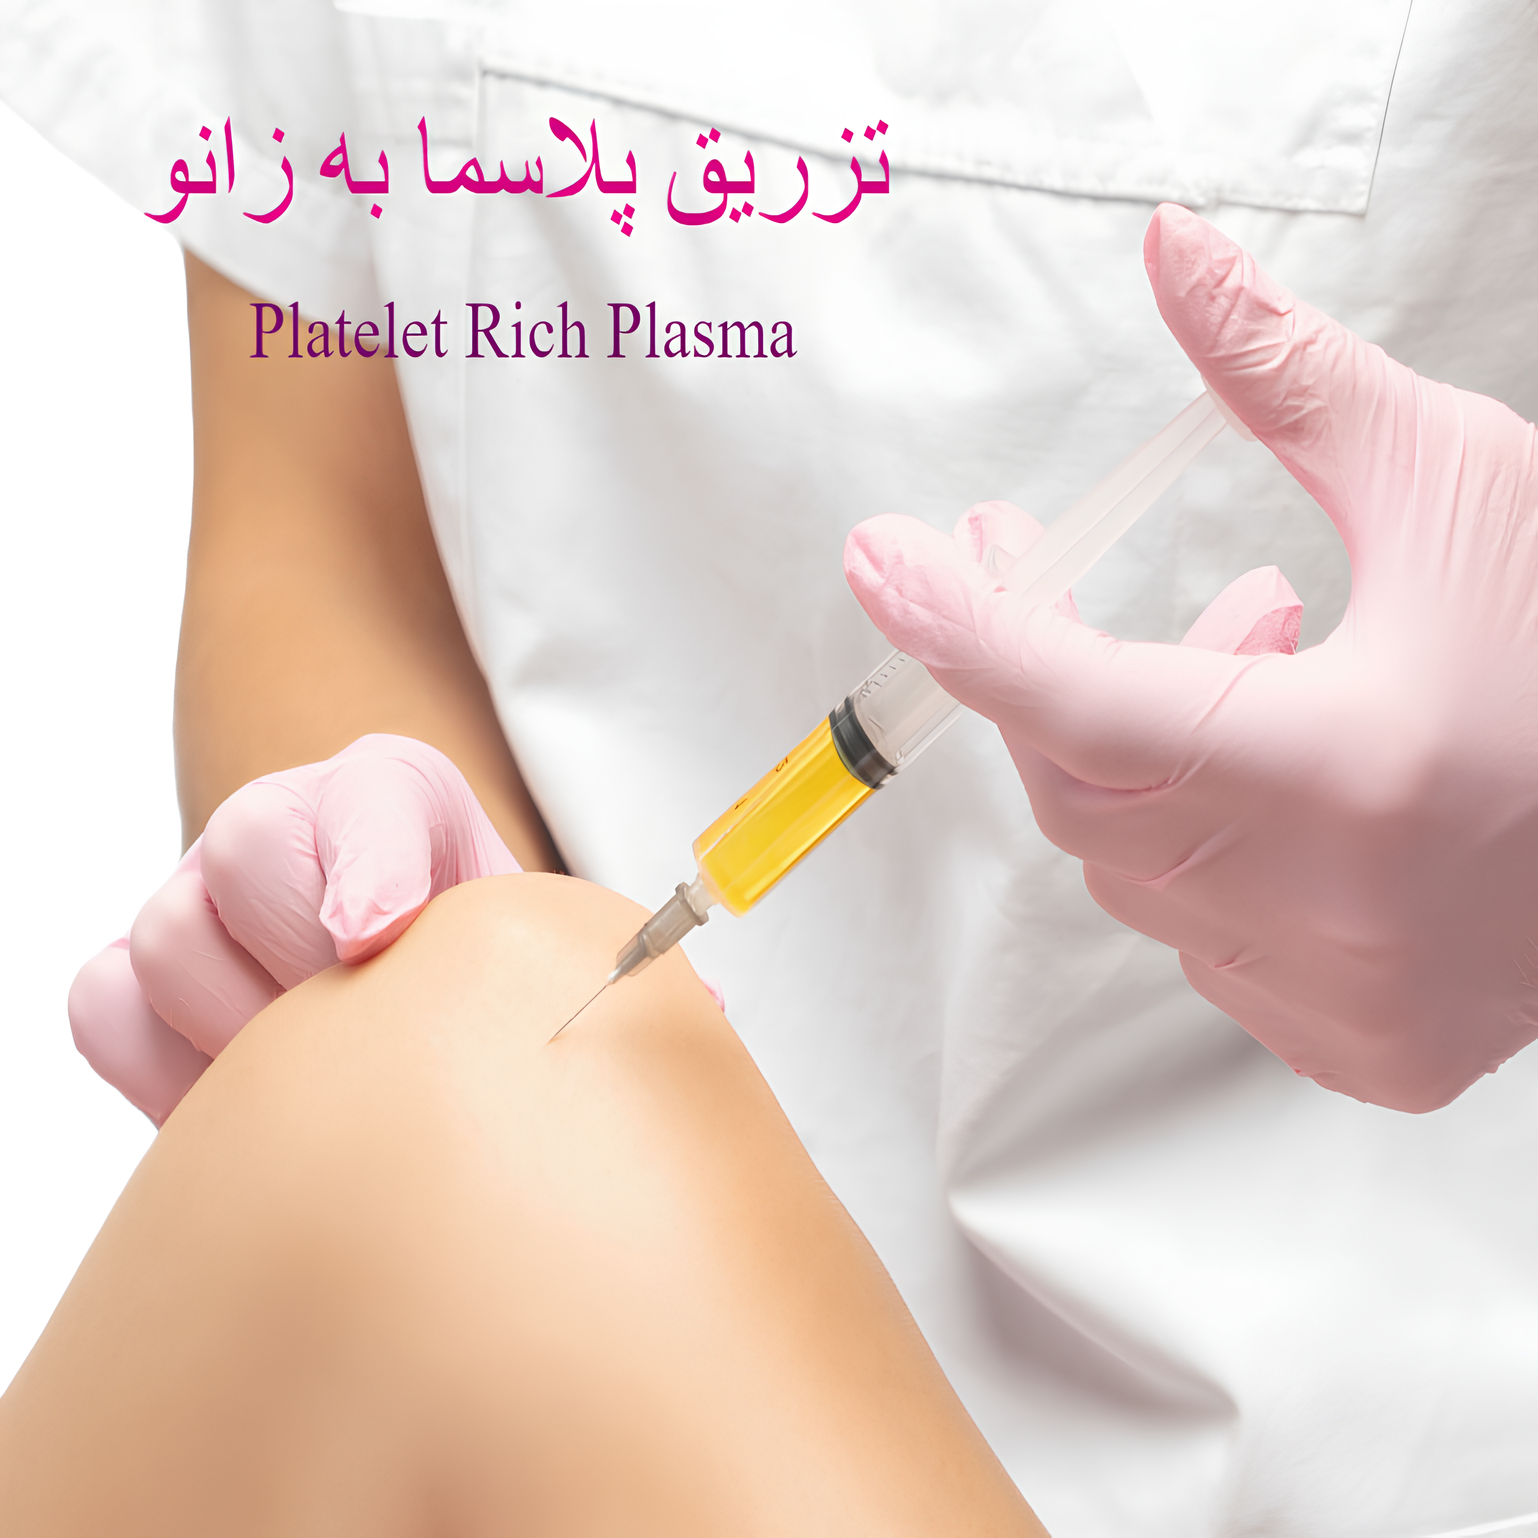

تزریق داخل مفاصل

کورتون برای کنترل التهابهای شدید و کاهش درد بهکار میرود. این داروها معمولا مستقیم داخل مفصل تزریق می شوند. ژل ، پی آر پی و ازون نیر داخل مفاصل بخصوص زانو تزریق می شوند. تزریق داخل مفاصل از روشهای موثر بهترین درمان آرتروز هست.